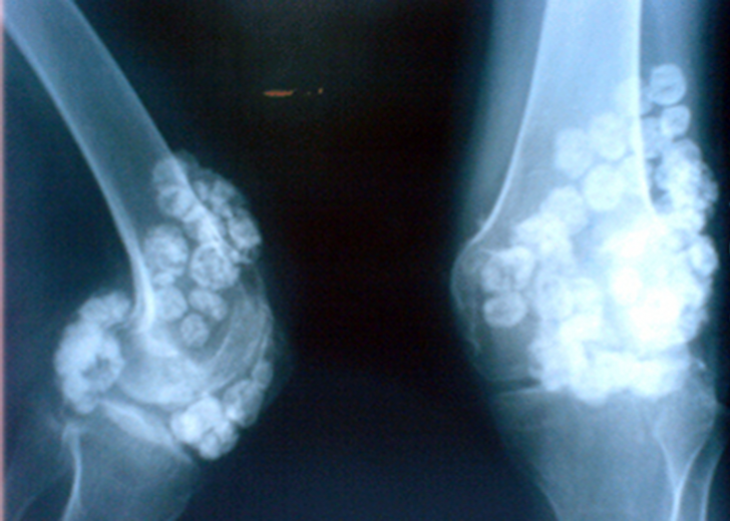

滑膜软骨瘤病是一种关节骨膜自限性增殖性的良性疾病,由滑膜内层结缔组织增生并化生成多数软骨结节,钙化、骨化而脱离滑膜,进入关节腔,形成大量游离小体。该病好发年龄为30~50岁,男性多于女...